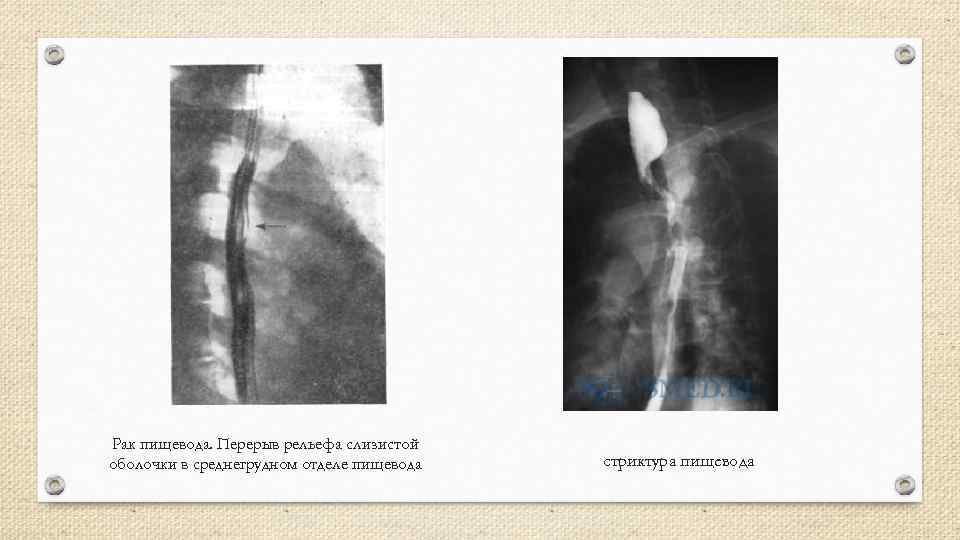

Рентгенологические исследования пищевода Выполняется в передней и боковой проекциях с 2 х сторон. Снимки осуществляют при тугом наполнении пищевода и после него – «двойное контрастирование» . Оценивают: • Изменение рельефа слизистой • Локализацию отмеченных изменений стенки • Степень и выраженность стеноза • Наличие изъязвлений, «свищей» (затекание контрастной массы в дыхательные пути или мягкие ткани) • Характер роста опухоли

Рентгенологические исследования пищевода Выполняется в передней и боковой проекциях с 2 х сторон. Снимки осуществляют при тугом наполнении пищевода и после него – «двойное контрастирование» . Оценивают: • Изменение рельефа слизистой • Локализацию отмеченных изменений стенки • Степень и выраженность стеноза • Наличие изъязвлений, «свищей» (затекание контрастной массы в дыхательные пути или мягкие ткани) • Характер роста опухоли

Рак пищевода. Перерыв рельефа слизистой оболочки в среднегрудном отделе пищевода стриктура пищевода

Рак пищевода. Перерыв рельефа слизистой оболочки в среднегрудном отделе пищевода стриктура пищевода